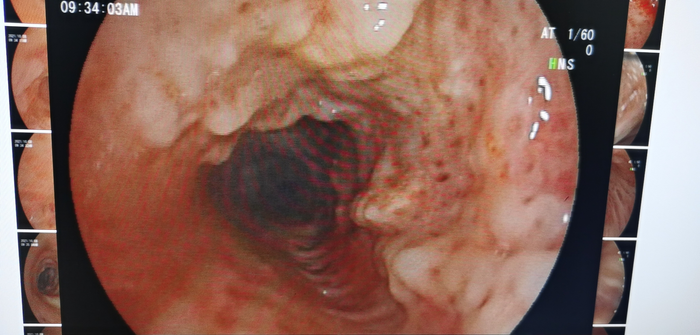

为了进一步明确,我们做了支气管检查,镜下发现支气管出现“惊奇”的一幕——气管、支气管黏膜下有多发性骨质或软骨组织结节状增生并突向管腔。

图12

看到这种病变是不是觉得很惊奇?能看出这是什么病吗?其实,这种病变常见于“骨化性气管支气管病”“气管支气管淀粉样变”等少见病。

我们再回看这个胸部CT的纵膈窗可以发现气管明显有气道壁后方膜部不受累的环状高密度影(钙化灶)。

图13

因为慢性气管支气管炎、老年性气管支气管等情况也可出现类似改变,很多人感觉司空见惯或认识不足常常不注意而漏诊。

我们在支气管镜下行活检,病理回报符合“骨质沉着性气管病”——即“骨化性气管支气管病”诊断成立。

图14